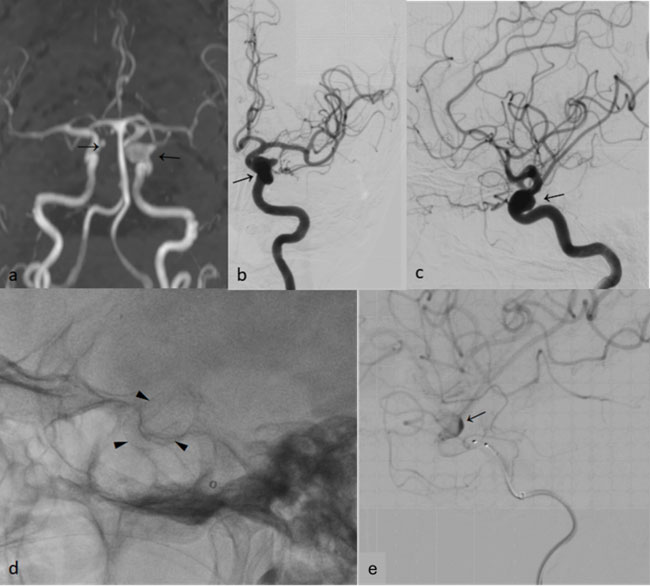

A 43-year-old woman from Andhra Pradesh presented with severe headache for 10 days and was diagnosed with aneurysmal SAH. She came to our hospital for further management. Her CT angiogram showed thin SAH in the anterior interhemispheric fissure and bifrontal sulcal spaces (Fig. 1a) with a small aneurysm in the left distal anterior cerebral artery (DACA). Digital subtraction angiography (DSA) showed a narrow-necked bilobed saccular aneurysm in the left DACA measuring 4 x 6 mm (Fig. 1b, c). The anatomy was favorable, and simple coiling was performed using two detachable coils (Target 3mm x 8cm, 2mm x 4cm, Stryker) achieving near-complete exclusion of the aneurysm (Fig. 1d-f). The patient had an uneventful recovery and was discharged on post-procedure Day 2.

Figure 1: (a) Non-contrast Computed Tomography (CT) brain showing SAH in the anterior interhemispheric fissure and bilateral frontal sulci (white arrow) (b, c) DSA Left ICA angiogram lateral and frontal projections showing a small bilobed saccular aneurysm (black arrows) in the precallosal segment of left ACA (d) Fluoroscopic roadmap showing deployment of coils (black arrow) within the aneurysm sac through a microcatheter (e, f) Post coiling left ICA angiogram lateral and frontal projections showing absent filling of aneurysm sac (black arrows).